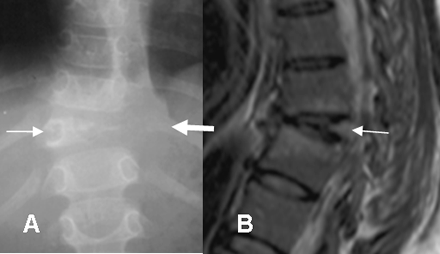

Fig 52 B. Osteomielitis TBC.

A: Rx AP y B: RM sagital en T2. Osteomielitis con pérdida de altura en el cuerpo de D11 (Flecha delgada) y masa de tejidos blandos paraespinal. (Flecha gruesa). En la RM se aprecia adicionalmente formación de cifosis.